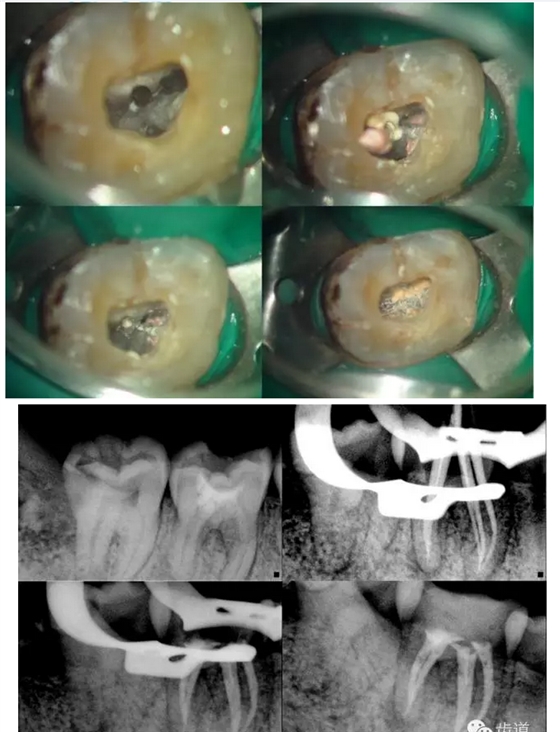

上頜第二磨牙:與上頜第一磨牙相似,多為3根管,偶見雙鄂根管;